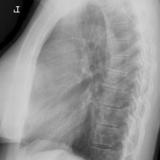

Case 9 Thymoma Lat

Date: 04/04/2010

Views: 3179